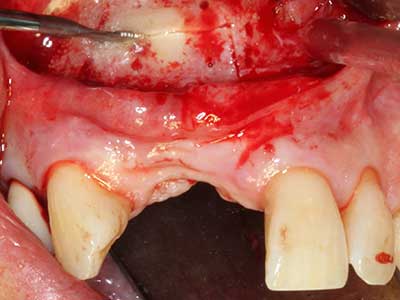

Bei der Knochenblockentnahme zeigen sich weitere Vorteile für die Piezochirurgie: Neben der bereits beschriebenen hohen Präzision bei der Osteotomie stellt sich gerade die Verwendung der dünnen Sägespitzen als besonders materialschonend heraus. Bei der Verwendung insbesondere von Lindemannfräsen sind mit deutlich höheren Entnahmeverlusten durch die dickere Instrumentenspitze zu rechnen (Lakshmiganthan, Gokulanathan et al. 2012). Die insbesondere bei retromolar entnommenen Blocktransplantaten notwendige basale Abtrennung wird durch speziell hierfür vorgesehene rechtwinklige Sägen erleichtert, so dass die Piezochirurgie als präzises, übersichtliches und sicheres Verfahren zur retromolaren Knochenblockgewinnung angesehen wird (Happe 2007) (Abb. 1-12).